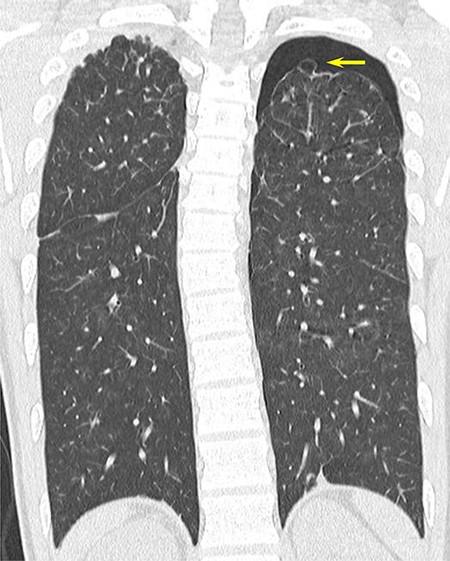

(A) CT scan showing PAVMs in the right upper lung (arrow) and (B) 3D-CT image. Green, PAVM; red, pulmonary artery; blue, pulmonary vein; yellow, trachea and bronchus.

recurrent intermittent epistaxis every few months and was monitored for PAVMs using computed tomography (CT) examinations every 6 months. He had a family history of HHT in his father and grandfather. After systemic examinations, he was diagnosed with HHT because he met the diagnostic criteria, including the presence of PAVM, recurrent epistaxis, and a family history of HHT, although genetic testing was not performed. A chest CT scan showed a left pneumothorax and apical bullae on both sides of the upper lobe (Fig. 1). In addition, a total of six PAVMs (four in the right lung, two in the left lung) were shown on the chest CT (Fig. 2). All PAVMs were located peripherally with the largest one being 3 mm in diameter. No AVM was detected in the brain or abdomen on CT. He was treated conservatively and then pneumothorax was improved. Six months later, the patient complained of cough and was diagnosed with pneumothorax by chest X-ray. To prevent the recurrence of the pneumothorax, the patient was offered video-assisted thoracic surgery. Intraoperatively, apical bullae and multiple telangiectasias were identified under the visceral pleura (Fig. 3). We performed wedge resection of the left upper lobe including the apical bullae. The postoperative histopathological findings of the resected specimen revealed pulmonary bullae (Fig. 4). The postoperative course was uneventful, and the patient was discharged on postoperative Day 2. He underwent catheter embolization for PAVMs in another hospital. His SpO2, which was measured before catheter embolization, was 97% on room air. There was no remarkable change in SpO2 after the intervention. No recurrence of the pneumothorax was observed during a 3-year follow-up.

In our case, we should pay attention to massive bleeding caused by damage to the PAVMs during pneumothorax surgery. In a previous report, 3D-CT was useful for determining the location of PAVMs [9]. The 3D-CT can support the surgeons to avoid careless grasping of the PAVMs and unintentional incomplete resection of PAVMs during the pneumothorax surgery. In our case, 3D-CT was useful for determining PAVMs preoperatively PAVMs.